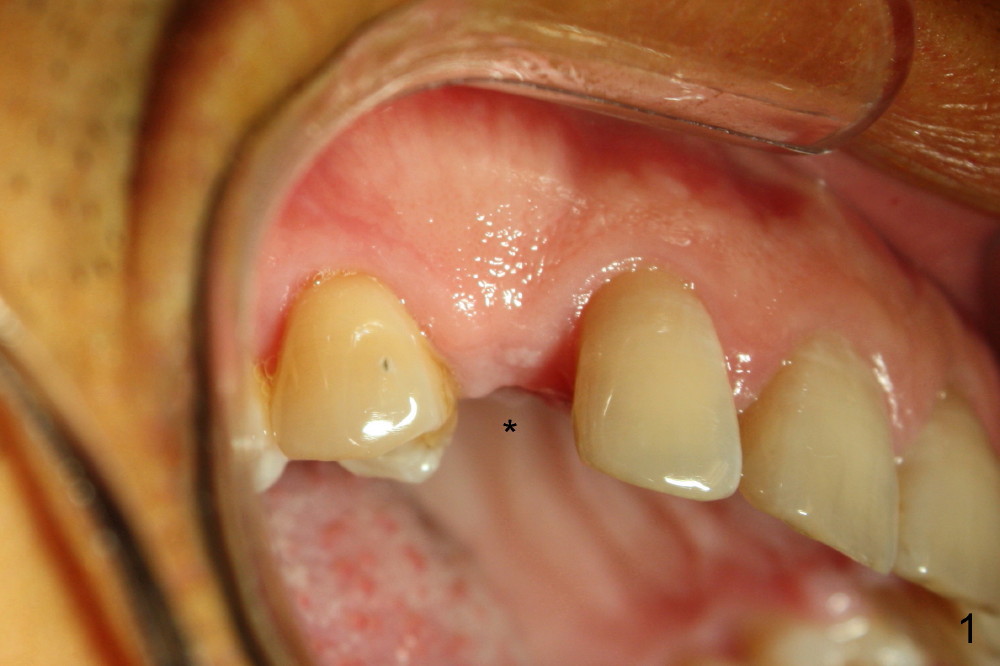

From prestige-dental-care.com.my

Dental Implant A case of an implant placement over missing canine Cuspid Tooth Implant Let’s delve into the causes, symptoms, treatment options, and recovery process for impacted canine teeth. The next most common are your cuspids aka “canine or i teeth”, which are located on the corners of your mouth. These teeth, also known as cuspid teeth or eye teeth, are the pointed teeth between the incisors and premolars. Problems with human canine teeth. Cuspid Tooth Implant.

Dental Implant A case of an implant placement over missing canine Cuspid Tooth Implant They play an essential role in biting and tearing food, but failing to emerge properly can lead to various problems. Robert “tito” norris shares techniques for predictable excellence when using a cuspid to replace a missing maxillary lateral incisor. They are also known as cuspids or eye teeth. The most common teeth to become impacted are your third molars, or. Cuspid Tooth Implant.

Dental Implant A case of an implant placement over missing canine Cuspid Tooth Implant Problems with human canine teeth can range greatly, from pain and discomfort due. Robert “tito” norris shares techniques for predictable excellence when using a cuspid to replace a missing maxillary lateral incisor. The maxillary and the mandibular first and second bicuspid each have their own unique characteristics. They are also known as cuspids or eye teeth. The most common teeth. Cuspid Tooth Implant.